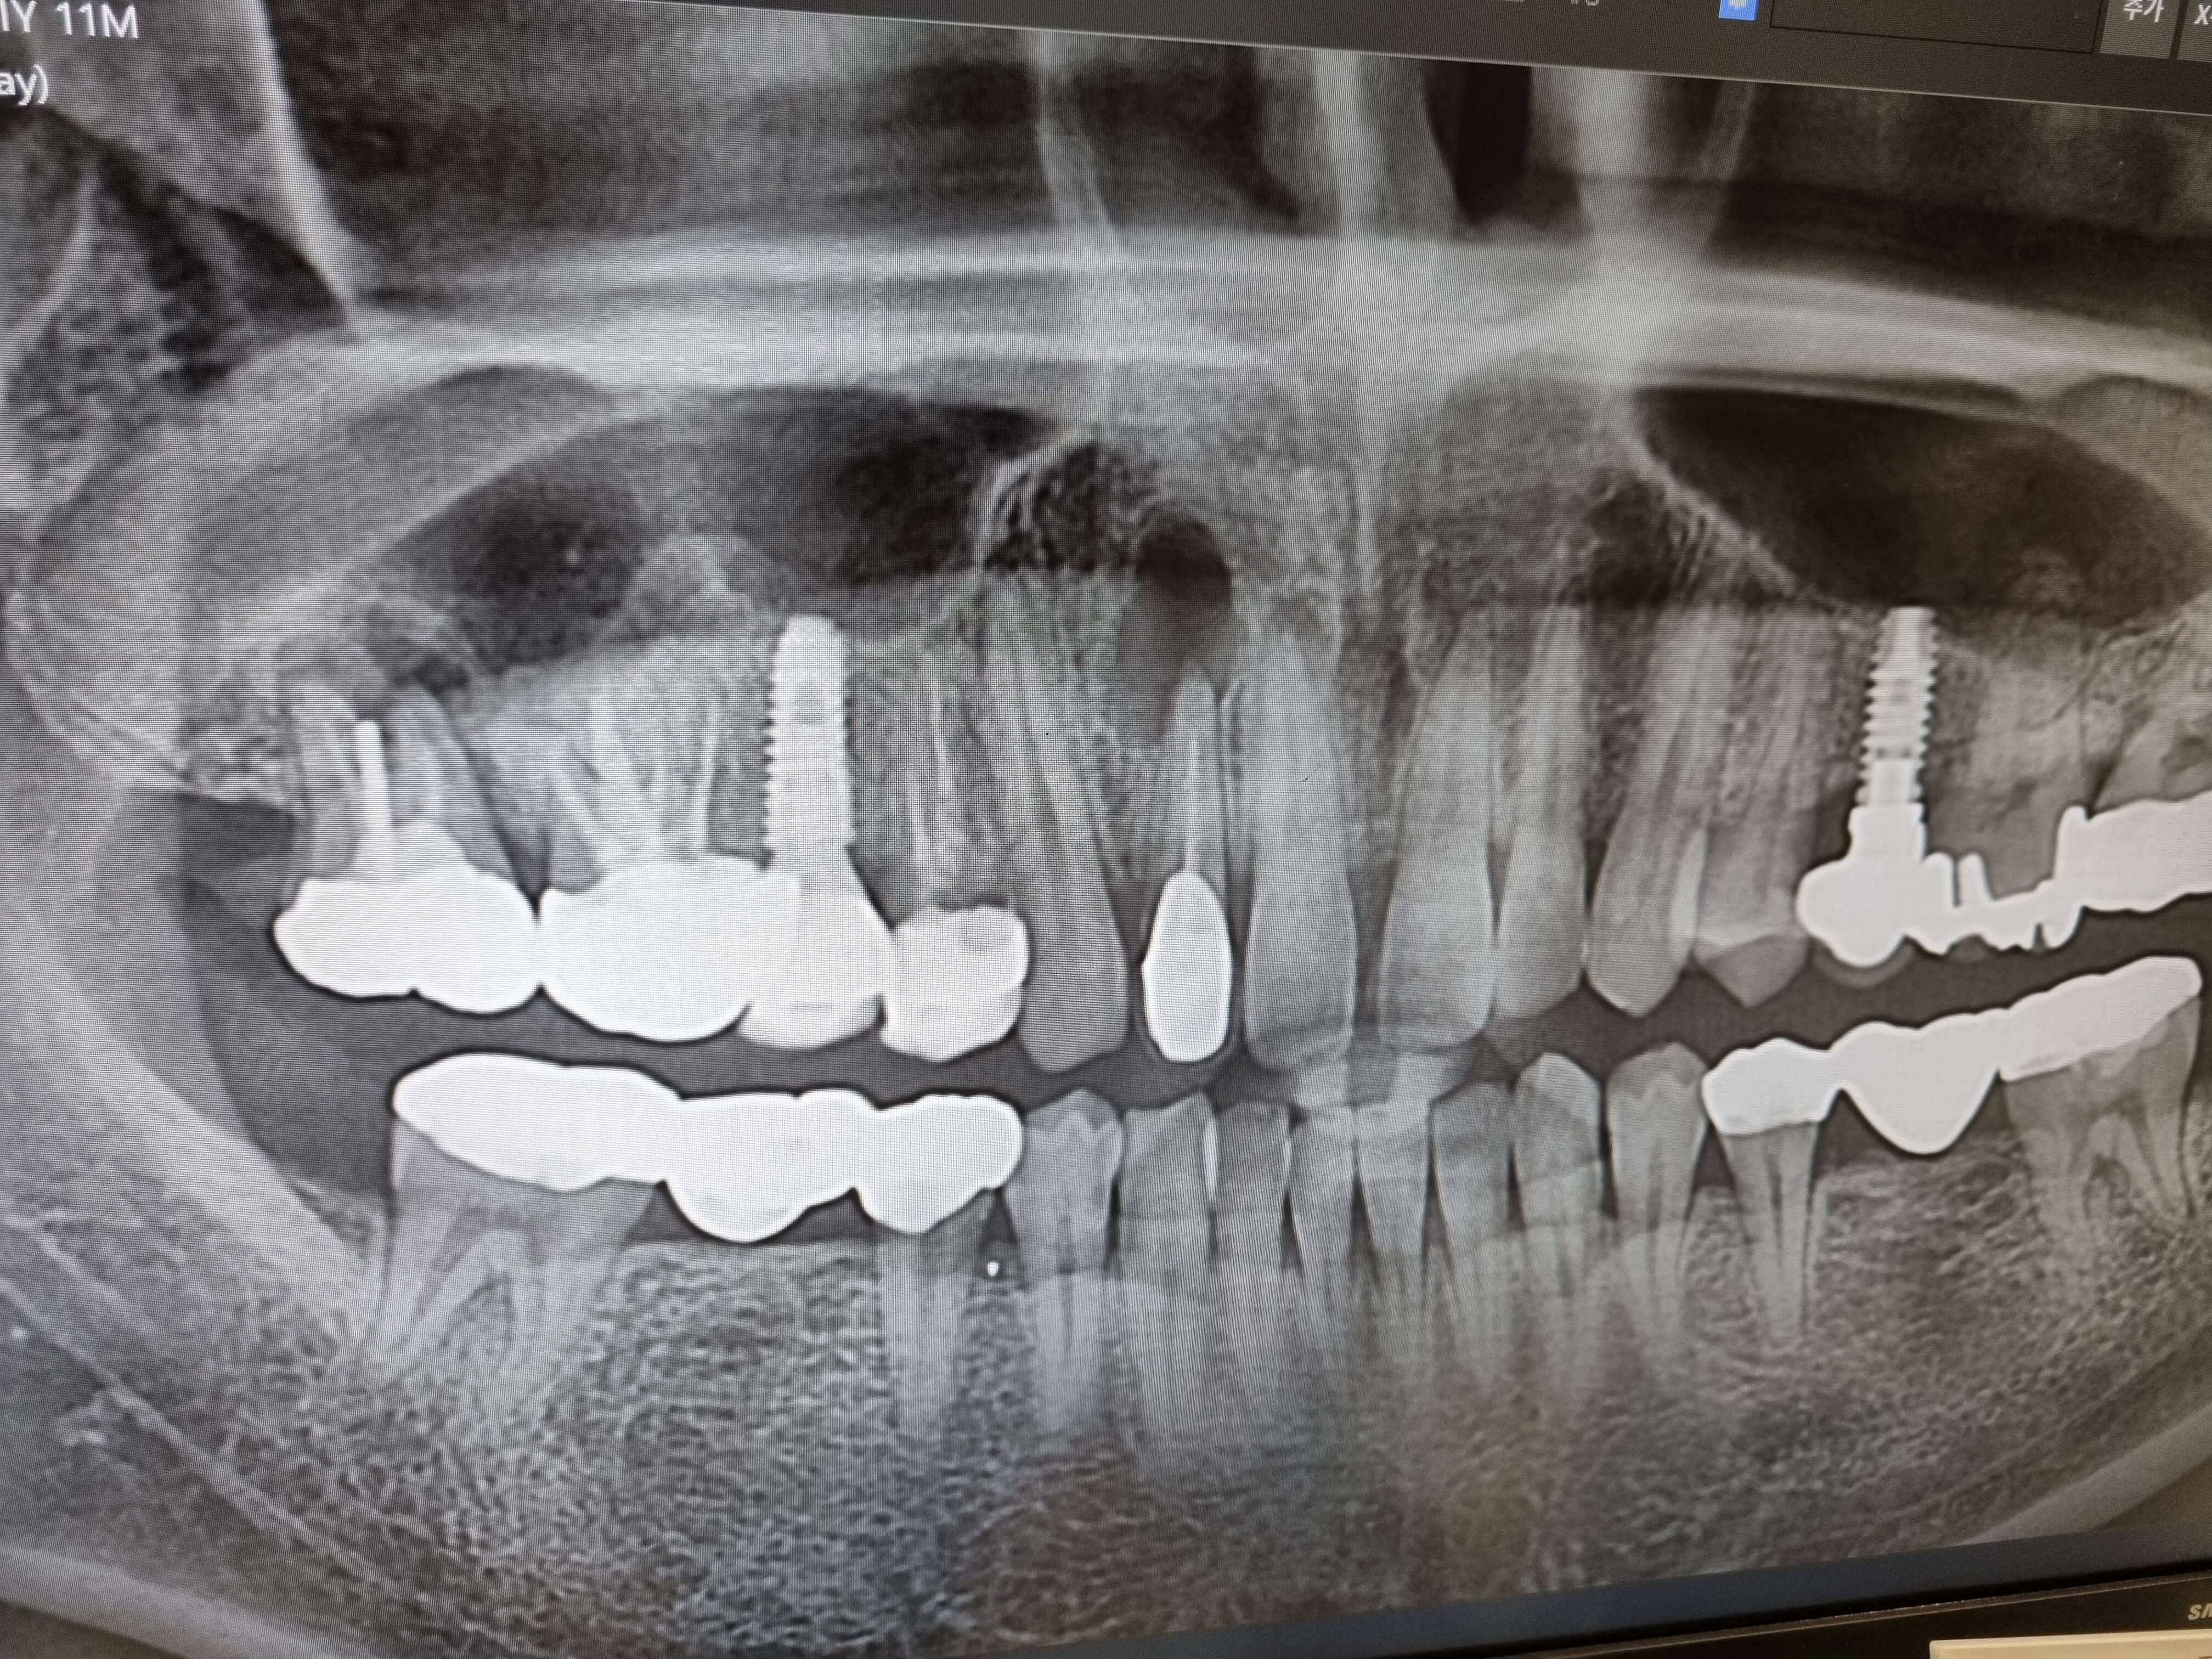

위 사진을 보시면 뼈가 뚤려 있습니다. 이것은 앞니 염증이 오래되다 보니 뼈를 녹여버리게 되었네요. 이것을 어떻게 치료해야 할지 치과선생님께 여쭈어 보니 해당 앞니 크라운을 사용할수 없으니 먼저 신경치료부터 해본다고 합니다.

염증 범위가 넓어 신경치료로 염증이 나아지지 않으면, 잇몸절단을해서 염증을 하나하나 다 긁어 낸다고 하네요. 이때 치아 뿌리를 자르고 잘살려 치료가 되면 새로운 크라운 정도로 하면 되는데 이것도 잘안되면 결국 뚤린 뼈에 치조골 이식을 해서 임플란트를 시행해야 한다고 합니다.

새로운 치과를 처음 방문하면 현재 치아상태를 알기위해 전부 사진을 찍고, 상황에 따라 CT까지 찍습니다. 저같은경우 2군데의 치아가 염증이 차있는걸로 확인되었고, 앞니쪽이 심해서 CT를 찍어본결과 참담한 결과가 나왔네요.

또한 오른쪽 임플란트 옆에 해넣은 크라운은 뿌리에서 염증이 발생해서 아깝지만 발치를 하는게 옳다고 여겨 그날 바로 발치를 했습니다. 이글을 적고 있는 오늘 발치해서 아프네요.